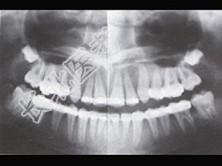

- 单项选择题患者,女, 40岁,因牙齿松动脱落、失眠、食欲不振1个月来院诊治。查体: 表情淡漠,牙槽骨处有压痛。骨骼X线摄片和123I放射性核素检查结果如图所示, 请问:该病例最可能的诊断为( )